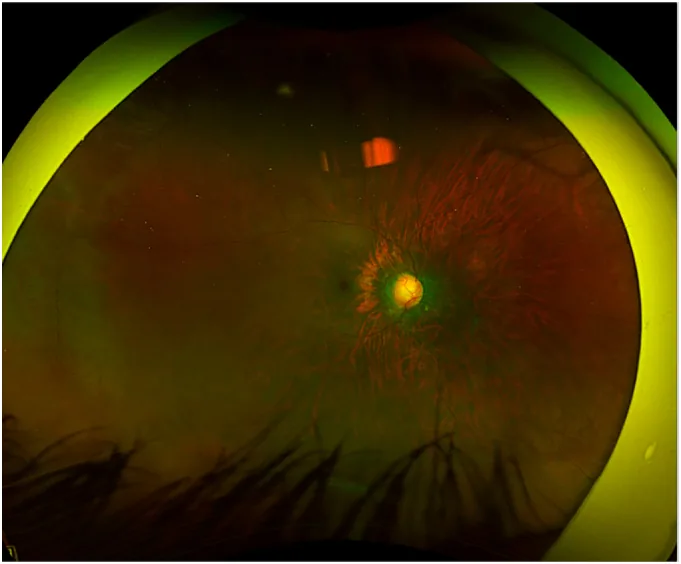

急性発作時の所見

眼圧:40 mmHgを超え、80 mmHgに達することもある1)2)

角膜:実質浮腫と微小嚢胞状浮腫を認める2)

瞳孔:中等度散瞳で対光反射が減弱・消失する2)3)

前房:中心部はある程度の深さを保つが周辺部が浅い。前房内炎症を伴う2)

緑内障斑:水晶体前嚢下の壊死。過去の発作を示唆する所見である2)

隅角:広範な虹彩線維柱帯接触を認める2)3)

急性発作時の所見

眼圧:40 mmHgを超え、80 mmHgに達することもある1)2)

角膜:実質浮腫と微小嚢胞状浮腫を認める2)

瞳孔:中等度散瞳で対光反射が減弱・消失する2)3)

前房:中心部はある程度の深さを保つが周辺部が浅い。前房内炎症を伴う2)

緑内障斑:水晶体前嚢下の壊死。過去の発作を示唆する所見である2)

隅角:広範な虹彩線維柱帯接触を認める2)3)